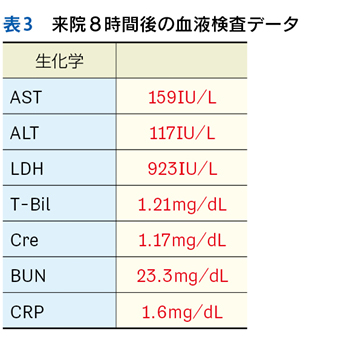

▶ 最後に,SQについて大切な点を補足しておく。それは「〇〇がない」という陰性情報も重要なSQとなりうる,ということだ。診断に関連する(鑑別に挙がっている疾患の確率を上げ下げする)陰性情報をpertinent negativesと言うが,これは時に陽性情報(「〇〇がある」)と同等,あるいはそれ以上に重要となることがある。「突然発症した腹膜刺激徴候のない重度の腹痛」「局所症状のない遷延性発熱」「単純CTで尿路結石がみられない突然の片側側腹部痛」のように,意味のある陰性情報をSQとして用いることで鑑別のフレームをぐっと狭めることができる。SQによる修飾の際には,こういったpertinent negativesも意識しておきたい。